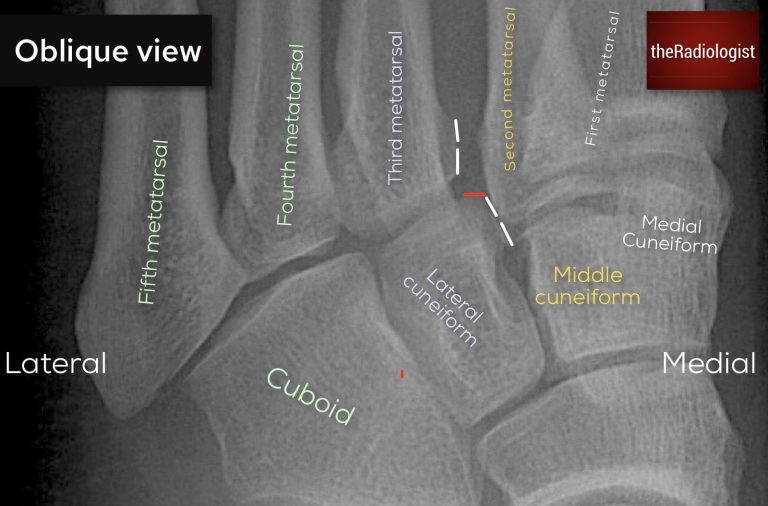

Annotated view of an oblique foot X-Ray

• Oblique view: the borders of the third metatarsal should line up with the lateral cuneiform.

Looking for Lisfranc injury (oblique view): on an oblique view look to see if the third metatarsal lines up with the lateral cuneiform.

Looking for Lisfranc injury (oblique view): in this case there is a subtle step between the lateral cuneiform and the third metatarsal. This is a Lisfranc injury.